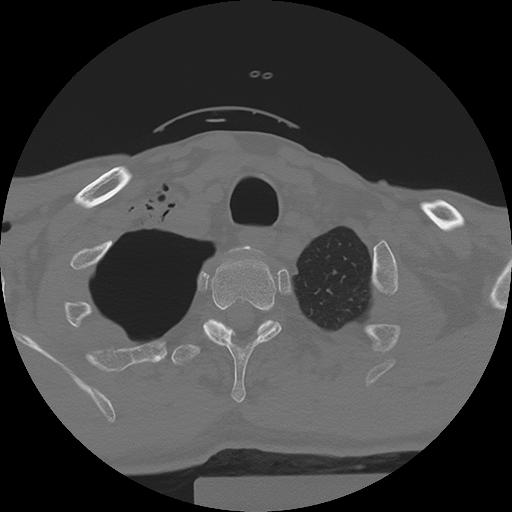

11 HUESO,,Axial,2.0,HUESO,,